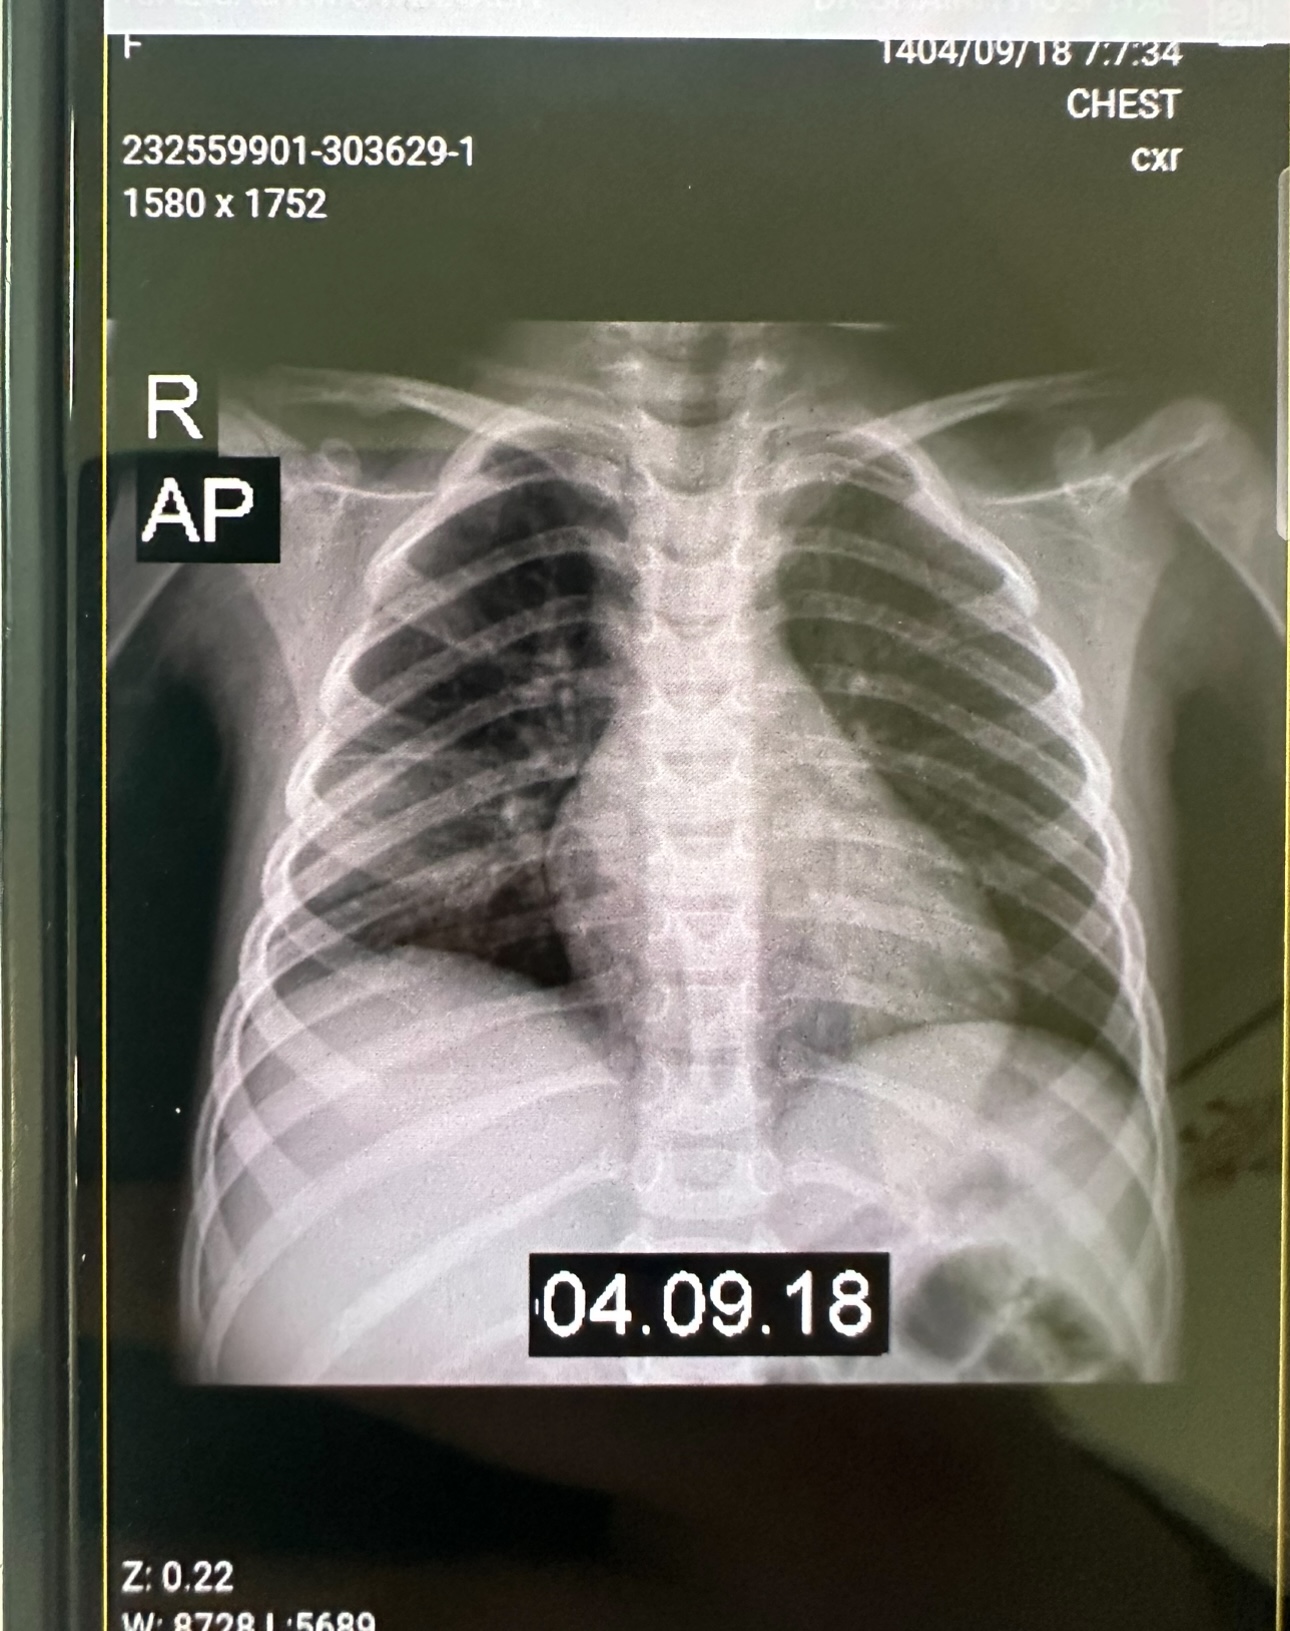

X-Ray: